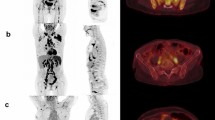

Table 3 shows comparison of risk groups classified according to the reference standard and each whole-body imaging modality. There was no significant difference in the concordance rate of the risk stratification between the three whole-body imaging modalities (concordance rate: 91.3% in skeletal survey, 82.6% in bone scan, and 97.8% in WB-MRI; overall p-value 0.066). Agreements in risk stratification assessed according to the reference standard and each whole-body imaging modality showed almost perfect agreement when using skeletal survey (weighted kappa of 0.88 with 95% CI of 0.75–1.00) and WB-MRI (weighted kappa of 0.98 with 95% CI of 0.93–1.00), and substantial agreement when using bone scan (weighted kappa of 0.66 with 95% CI of 0.44–0.88; Table 3). Representative cases are shown in Figs 2 and 3.

Skeletal survey (a), bone scan (b) and STIR coronal images of WB-MRI (c–e) of a 6-year-old boy with a pathologically-confirmed LCH lesion in the right clavicle. The lesion in the clavicle (solid arrow) was detected in all three imaging modalities (a–c); however, the lesion in the T8 vertebral body, appearing as a partially collapsed vertebral body, was noted only on skeletal survey (a) and WB-MRI (d), and the lesion in right first rib was noted only on WB-MRI (e). Although an additional lesion in the right first rib was detected on WB-MRI but not by the skeletal survey, the risk stratifications by WB-MRI and skeletal survey were identical for single system LCH with multiple bone lesions or CNS risk lesions.